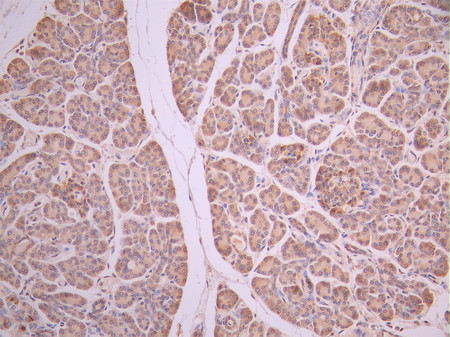

• IHC image of CSB-RA238916A0HU diluted at 1:100 and staining in paraffin-embedded human pancreatic tissue performed on a Leica BondTM system. After dewaxing and hydration, antigen retrieval was mediated by high pressure in a citrate buffer (pH 6.0). Section was blocked with 10% normal goat serum 30min at RT. Then primary antibody (1% BSA) was incubated at 4°C overnight. The primary is detected by a Goat anti-rabbit polymer IgG labeled by HRP and visualized using 0.05% DAB.